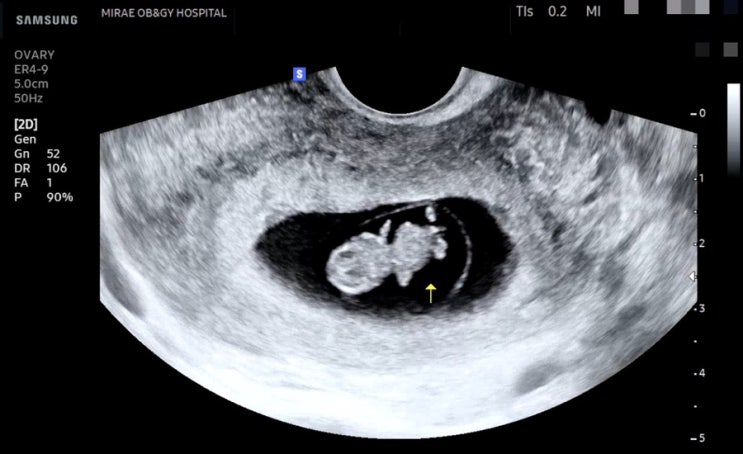

[임신 12주차]증상,드디어 첫 정밀초음파, 성별❣️

엘디와 함께한지 벌써 12주 째! 안정기 시작으로 불리우는 주수이고 나는 드디어!!! 크녹산과 이별했다~~~ ...